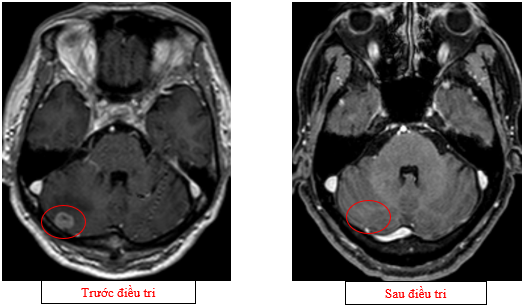

-         Cộng hưởng từ sọ não (08/2025): Nhu mô bán cầu đại não, tiểu não phải, thái dương trái có các nốt lớn nhất đường kính 13mm, giảm tín hiệu trên T1W, tăng tín hiệu trên T2W, phù não xung quanh, ngấm thuốc mạnh sau tiêm – theo dõi tổn thương thứ phát

Hình 06: Bán cầu đại não, tiểu não phải, thái dương trái có các nốt lớn nhất đường kính 13mm, giảm tín hiệu trên T1W, tăng tín hiệu trên T2W, phù não xung quanh, ngấm thuốc mạnh sau tiêm

-         Chụp cộng hưởng từ sọ não (11/2025):Nhu mô não hình dạng và cấu trúc bình thường, tín hiệu đồng nhất, ranh giới chất trắng và chất xám rõ. Không thấy tổn thương khu trú hoặc lan tỏa

Hình 13: Không còn thấy tổn thương di căn não vùng bán cầu tiểu não sau điều trị trên phim chụp

Hình 14: Không còn thấy tổn thương di căn não vùng thùy đỉnh sau điều trị trên phim chụp

+      Trên phim chụp cộng hưởng từ sọ não: không còn ghi nhận các ổ tổn thương di căn di não, phù não.